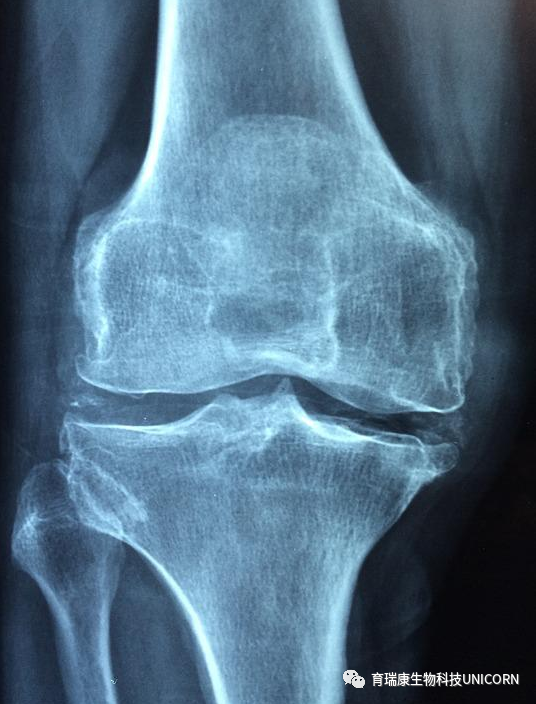

41例患者干细胞治疗骨关节炎有效

2020年《中国实用医药》杂志第25期,张婷等人发表了文章《间充质干细胞治疗骨关节炎的效果和机制》再次证实了干细胞治疗骨关节炎的有效性。

2019年3月~2020年3月,收治的82例骨关节炎患者,根据疗法不同分为A组与B组,各41例。A组患者予以塞来昔布治疗,B组患者予以塞来昔布联合脐带间充质干细胞治疗。结果B组患者的总有效率90.24%,高于A组的73.17%,差异具有统计学意义(P<0.05)。

结论表示间充质干细胞治疗骨关节炎的效果显著,且可有效缓解关节疼痛,改善关节功能,抑制关节骨滑膜炎症反应,促进软骨恢复,值得推行。